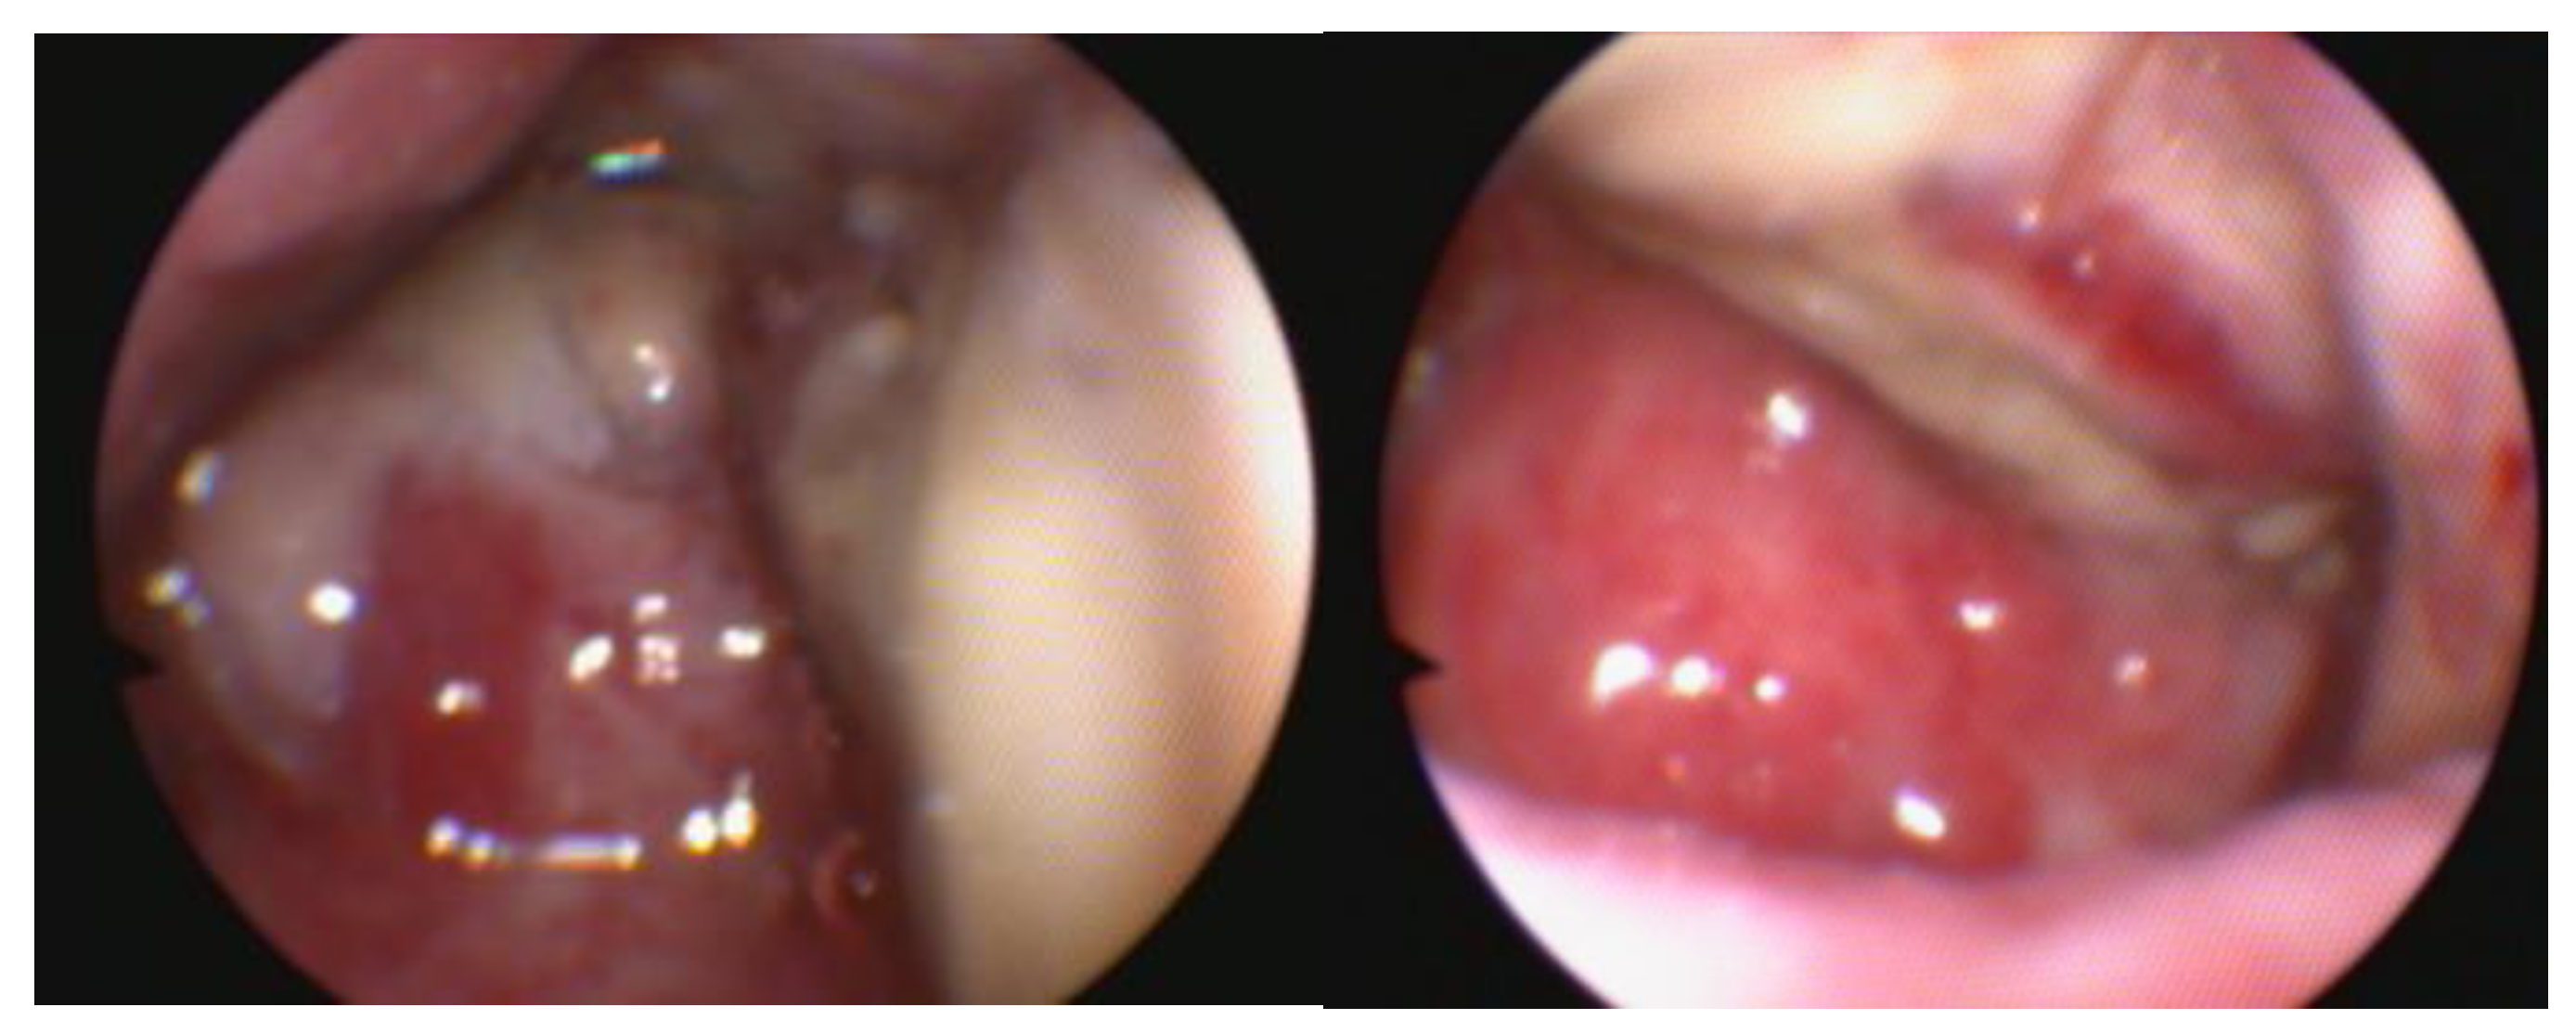

When examined, the vestibular-vaginal junction should be a single, smooth, continuous, symmetrical, and distensible opening. Asymmetry suggests the existence of tumours, infections, or injuries. A narrower, barely distensible aperture characterises a vestibular-vaginal stricture. A smaller, minimally extensible opening contains vestibular constriction. If the vestibular-vaginal junction divides into two or more openings, consider a diagnosis of vaginal septum or vaginal duplication Figure 5 [14].

Figure 5. Endoscopic view of a complete vaginal septum in a 5 years old Amstaff female dog which was referred for pre-breeding clinical exam.